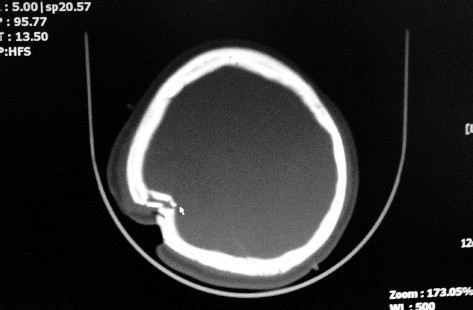

送医时文文的头部扫描影像显示,其头顶有一处长达10多厘米的伤口,并伴有颅骨骨折,一片长达6.5厘米左右的骨片插入脑组织约1厘米。

送医时文文的头部扫描影像显示,其头顶有一处长达10多厘米的伤口,并伴有颅骨骨折,一片长达6.5厘米左右的骨片插入脑组织约1厘米。朱斌/摄

文文脑科手术的主刀医生、温医附一院急诊创伤外科副主任医师赵峰介绍:入院时文文的头顶有一处长达10多厘米的伤口,并伴有颅骨粉碎性和凹陷性骨折,一片长达6.5厘米左右的骨片穿破脑膜,插入脑组织约1厘米。现在,文文的苏醒确实是个好消息,但并不意味着她的病情完全好转。因为长时间未进食进水,文文目前还非常虚弱,需要一段时间的调理和恢复。而且文文的心跳还是有点快,体温偏高,最关键的是不能出现严重的感染,这些都需要进一步的观察。所以,现在说她已经脱离生命危险,为时尚早。